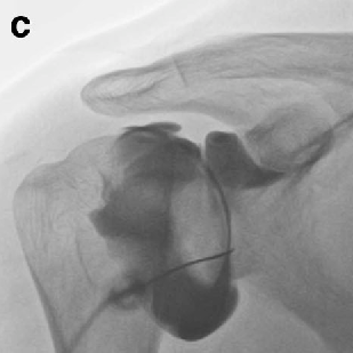

어깨 관절낭 수압 팽창술

염증에 의한 관절낭과 회전근개의 유착을 제거하기 위해 유착을 녹이는 효소제를 주사 할 수 있으며 염증과 부종을 줄여주기 위해 항염증제를 같이 주입합니다. 어깨 관절낭에 최대한 많은 주사액을 주입함으로써 물리적, 화학적으로 유착을 박리하고 조직의 염증과 부종을 줄여줍니다.